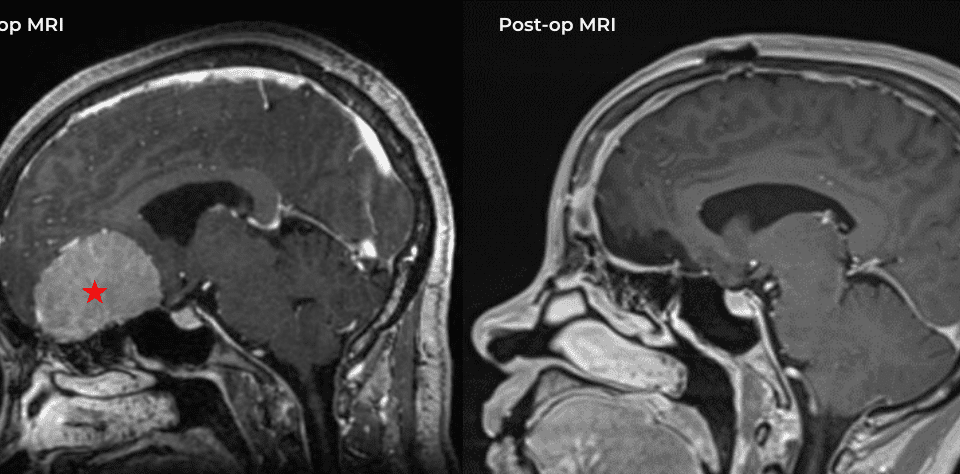

This is a 49-year-old otherwise healthy female who presented with bifrontal and retro-orbital headaches, behavioral changes, and forgetfulness. Symptoms have been progressively worsening over the past […]